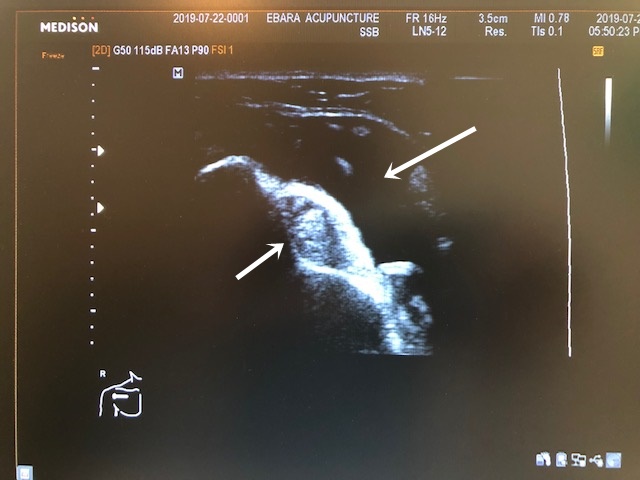

服を脱いでもらい視診を行うと肩の前が腫れており、超音波エコーで確認すると、二頭筋の長頭が腫れており、関節内にも水が溜まってい様子が確認できました。

下の矢印の先の白い部分が二頭筋腱・上の矢印の先の黒い部分が関節内の水